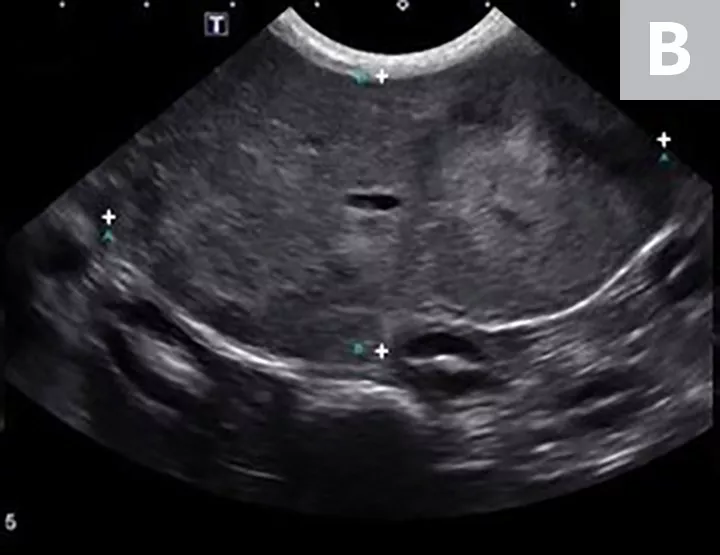

FIGURE 11A

Imaging of a 1-year-old neutered male standard poodle presented with anorexia, lethargy, vomiting, hypoalbuminemia, hypoproteinemia, and cranial abdominal organomegaly. Transverse (A) and sagittal (B) ultrasound of the liver and gallbladder (GB). The liver is enlarged (with increased distance off the stomach from the diaphragm, rounded borders, and extension ventral to the stomach), diffusely hyperechoic, and homogenous. The gallbladder is moderately distended with a normal wall and content. Radiographs demonstrate hepatomegaly and splenomegaly (C). Abdominal ultrasound images revealed splenic enlargement with a mildly mottled architecture and a solitary hypoechoic nodule (D; arrowheads). The pancreas is enlarged and lobulated with multiple hypoechoic tracts and a peripheral capsule (E; between electronic cursors [X’s]). The jejunal lymph nodes are severely enlarged (F; between electronic cursors [X’s]), more than expected for a young dog. The combination of severe hepatosplenomegaly and lymphadenomegaly make systemic disease (eg, infectious, neoplastic) most likely. The appearance of the pancreas is due to pancreatic edema secondary to hypoproteinemia. Acute liver injury was diagnosed, and lymphoma was diagnosed based on hepatic and splenic cytology.